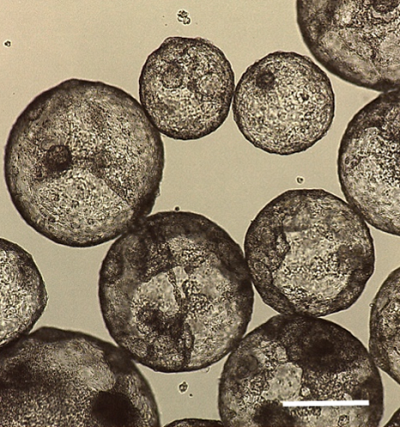

L'image montre des agrégats 3D en suspension (également appelés embryoïdes) de cellules souches pluripotentes induites et de cellules auxiliaires. Les cellules auxiliaires de ces agrégats 3D favorisent la génération de cellules souches musculaires à partir des cellules CSPi. Chacun de ces agrégats est composé de centaines de milliers de cellules.

Photo : Fournie

Protocole de création

Pour que la greffe soit efficace, les cellules souches greffées sont générées à l'aide de deux autres types de cellules en agrégats 3D. Cela comprend un type de cellule produisant de grandes quantités de tissu conjonctif et un type de cellule que l'on trouve généralement dans les vaisseaux sanguins. Ensemble, elles soutiennent la génération de cellules souches musculaires à partir des cellules CSPi. L’équipe du Pr Bentzinger et du Nestlé Institute of Health Sciences ont développé le protocole pour que les agrégats puissent se former dans un environnement liquide. Cela comporte plusieurs avantages, tels que la création de cellules souches pures, la facilité de reproduction et la production d’un bon nombre d’agrégats dans un espace restreint.